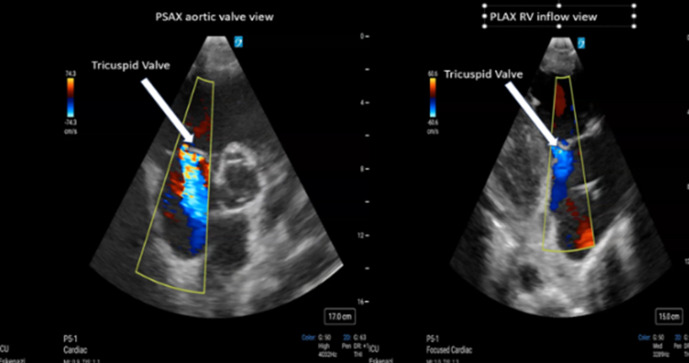

Point-of-care ultrasound (POCUS) is a powerful diagnostic tool that combines image acquisition with bedside interpretation, enabling physicians to make rapid diagnoses at the bedside (1). Over the last decade, the popularity of POCUS has surged because of its versatility and the immediate insights it provides in clinical decision making (1). However, basic POCUS does not provide important hemodynamic information, such as intracardiac pressures, stroke volume, or valvular regurgitation assessment. Critical care echocardiography (CCE) becomes indispensable as a specialized application of POCUS focused on using Doppler techniques to provide detailed hemodynamic assessments in critically ill patients (2). Teaching hemodynamic evaluation in CCE, such as estimating right ventricular systolic pressure (RVSP), is a challenging yet essential aspect of modern critical care education. RVSP is used to assess the presence of pathologic elevation in right ventricular afterload, which has significant clinical implications for critically ill patients. Deriving RVSP requires understanding ultrasound physics, fluid mechanics, and Doppler techniques and mastery of cardiac image acquisition (3-4). These complex skills are not just important but crucial for effectively managing critically ill patients in the intensive care unit (ICU). In this edition of "How I Teach," we introduce our methodology for instructing learners in our ICU on RVSP estimation using CCE. We use hands-on ultrasound training and e-learning strategies to optimize knowledge retention, ensure accurate interpretation, and promote practical application.